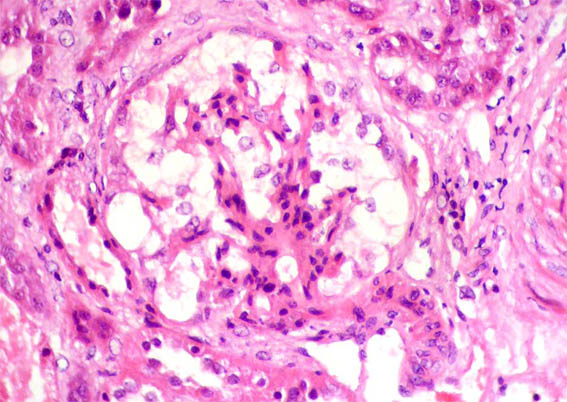

Figure 1. H&E , X400.